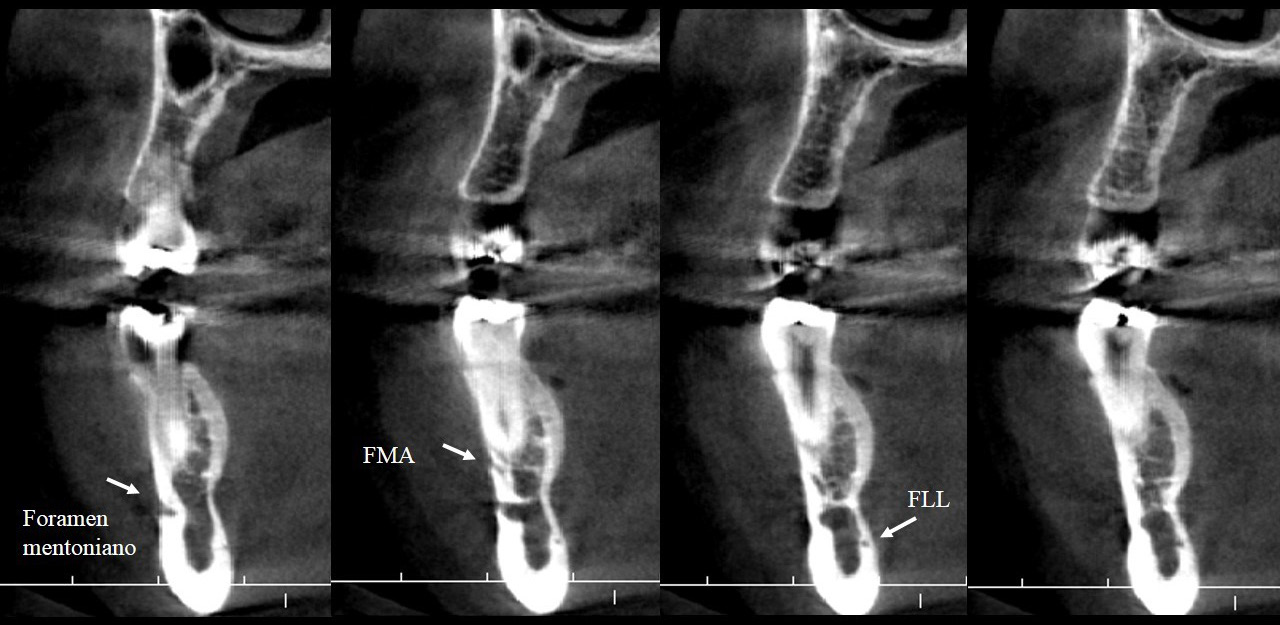

La mandíbula se origina del primer arco braquial, tiene una osificación mixta y su crecimiento es con dirección hacia abajo y adelante (1). El nervio dentario inferior ingresa a la mandíbula a través del foramen mandibular hacia el conducto dentario inferior (CDI). Se ramifica en dos nervios, el nervio incisivo que continúa por el conducto incisivo y el nervio mentoniano que emerge por el foramen mentoniano (FM) dando suministro sensorial al mentón, labio inferior y encía vestibular de los dientes anteriores del mismo lado de la mandíbula (2, 3,4).

Es posible también encontrar más forámenes, a éstas foraminas adicionales se les denomina foramen mentoniano accesorio (FMA). Es importante distinguir entre un FMA y un foramen nutricio (2). Un FMA verdadero parte del CDI, mientras que un foramen nutricio, si bien aporta nutrientes a la mandíbula, no tiene comunicación con el CDI (6).

También se pueden encontrar pequeñas foraminas en la superficie lingual de la mandíbula; según su localización éstas se pueden clasificar en foramina lingual medial, si se encuentra en la línea media o cerca a ésta, y foramina lingual lateral (FLL), si se encuentra lateral a la línea media (16, 17). A través de la FFL ingresan ramas de la arteria sublingual, submental (16) y ramas del nervio milohioideo y lingual (18). Su estudio no puede realizarse mediante radiografías, se recomienda usar TCHC y visualizar el FLL en cortes axiales y transaxiales (18) para verificar su comunicación con el CDI (17).

El FM es un hito anatómico a través del cual emergen el nervio mentoniano y su paquete vascular, su posición y forma varían mucho en la literatura (1,5). Es posible encontrar más forámenes en la zona, estos se llamarán FMA si se comprueba su continuidad con el conducto mentoniano o con el CDI, y se llamarán FLL si emergen en la superficie lingual distal a la zona de caninos y se continúan con el CDI. Si estos forámenes extras no presentan una continuidad con el CDI o con el conducto mentoniano, se les denominará foramen nutricio (14, 16). Su detección es de gran importancia en el planeamiento de diversos tratamientos para evitar disturbios sensoriales y accidentes, ya que la injuria de un foramen con más de 1 mm de diámetro puede causar una hemorragia importante (16,17), por ello el propósito de este estudio fue evaluar la posición, forma y variantes anatómicas del foramen mentoniano.

La frecuencia de los FMA reportada en la literatura varía mucho, desde 1,76% (13) hasta 55% (1), además de la diversidad étnica, esta variación puede deberse a diferencias en la metodología y en la definición de los FMA. El uso de las imágenes renderizadas no es metodológicamente correcto para el estudio de los FMA, ya que un foramen menor de 1.3 mm2 no se detectará fácilmente (6), además que no nos permiten descartar que se trate realmente de un foramen nutricio (2,6,14,16), sin embargo, este método fue utilizado en las investigaciones de Cabanillas Padilla (1) y Alam (8). No se encontró asociación estadísticamente significativa entre la presencia del FMA con el sexo, ni con el lado, lo que coincide con los hallazgos de Aytugar (2), Lam (6) y Xiao (14) (figura 5).

No hay mucha evidencia científica que refiera una presencia simultánea de FMA y FLL, Krishnan (17) encontró una asociación entre la presencia de ambas variantes anatómicas. En su estudio el 42,9% de los casos que presentaba FLL tenía también un FMA, este hallazgo es similar a la distribución observada en el presente trabajo (figura 6). En la muestra de este estudio se pudo encontrar combinaciones de variantes anatómicas no descritas en otras publicaciones, como la presencia de foramen doble y FLL doble en 3 casos y la relación de foramen triple y FLL encontrada en un caso (figura 7 y figura 8).